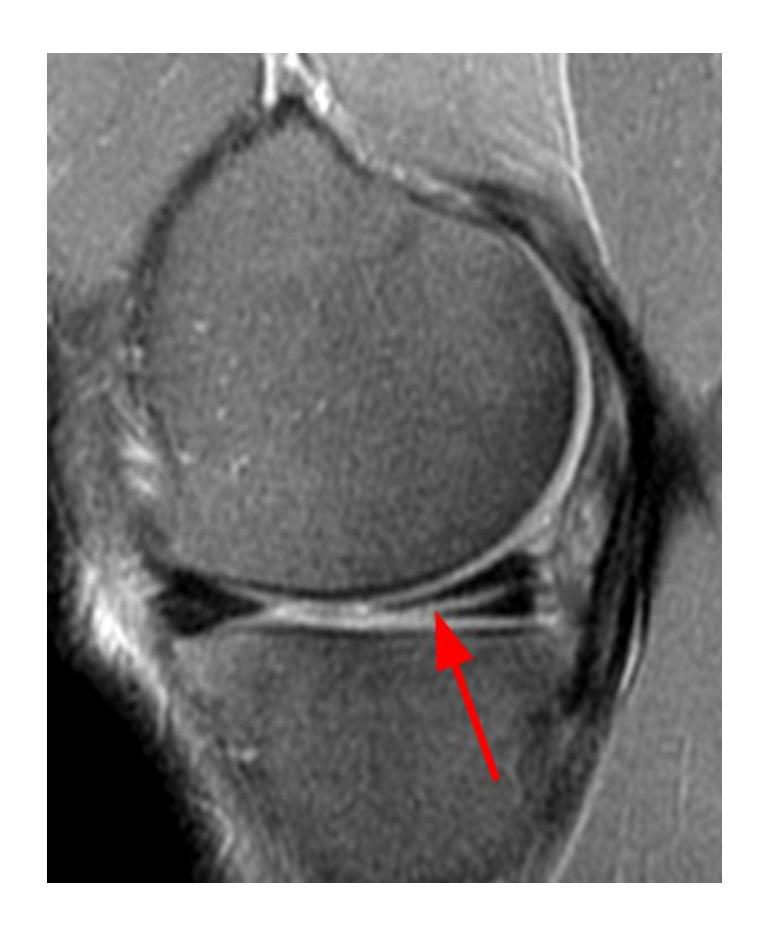

What pathology is seen in this MRI of an 18-year-old male who twisted his knee?

- Posterior horn meniscal tear

- Bucket-handle meniscal tear

What is the significance of the double PCL sign?

- Indicates bucket-handle meniscal tear

What does the white arrow indicate in this image?

- Posterior meniscus horn

What is the diagnosis shown in these images?

- Posterior meniscus horn tear